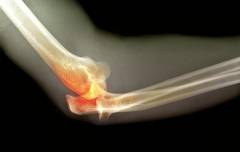

Перелом костей локтя — распространенная травма, возникающая при механическом воздействии. Перелом может произойти при падениях, ударах или компрессии.

При переломе возникают боли, отек, подкожные кровотечения и ограничение движений. В некоторых случаях перелом может быть открытым.

Перелом может затрагивать один или несколько участков костей, формирующих локтевой сустав, с образованием острых осколков, повреждающих соседние структуры.

Перелом костей локтя

Перелом костей локтя — распространенная травма, возникающая из-за механического воздействия: ударов, падений или компрессии сустава. Это состояние связано с повреждением костной структуры элементов сустава. Переломы локтя часто происходят в результате дорожно-транспортных происшествий, спортивных травм или падений на скользкой поверхности.

Перелом локтя вызывает сильные боли в суставе, усиливающиеся при нажатии. Сустав может отекать, а вокруг него появляются синеватые подкожные кровоизлияния. Пациенты испытывают трудности с активными движениями. В некоторых случаях костные фрагменты могут быть видны через кожу. Если наблюдается наружное кровотечение, перелом классифицируется как открытый.

Диагностика переломов костей локтя проста и не вызывает затруднений. Она основывается на лучевых методах исследования, таких как рентгенография и компьютерная томография, которые фиксируют поврежденные участки.

Методы диагностики переломов костей локтя:

- Анамнез. При сборе анамнеза выявляются признаки перелома в области локтя, причины болей и время их появления.

- Внешний осмотр. Этот метод позволяет обнаружить гематомы, наружное кровотечение, отечность и болезненность в суставе.

- Рентгенография и компьютерная томография. Эти исследования определяют локализацию и тип перелома, оценивают степень тяжести и выявляют возможные осложнения.